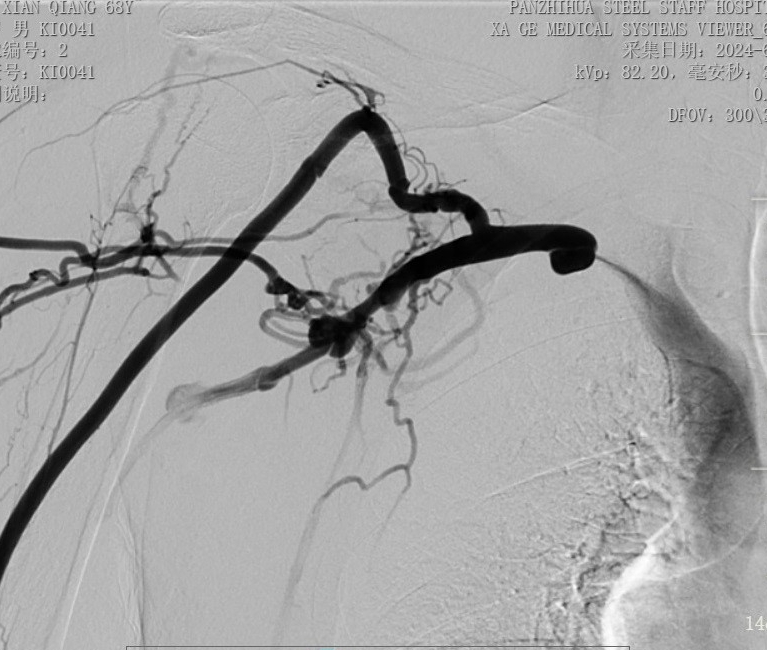

術(shù)后造影顯示:右鎖骨下靜脈狹窄完全打開

手術(shù)中,主刀醫(yī)生唐靜通過DSA順利對人工血管中形成的血栓進(jìn)行了取栓。之后,在中心靜脈造影下,發(fā)現(xiàn)患者中心靜脈外周有2cm的狹窄,尤其是右鎖骨下靜脈得狹窄已經(jīng)嚴(yán)重到幾乎閉塞,針眼大小的縫隙僅能容下導(dǎo)絲通過。經(jīng)過反復(fù)嘗試與不懈努力,終于將導(dǎo)絲置入,并用12 *40mm的球囊擴(kuò)張,右鎖骨下靜脈成功開通,患者透析的通道打開了。術(shù)后,家屬看著消腫的手臂感激萬分,眼淚奪眶而出。